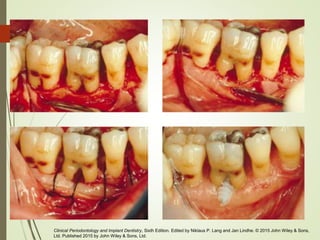

Hemisección en molares inferiores

Clinical Periodontology and Implant Dentistry, Sixth Edition. Edited by Niklaus P. Lang and Jan Lindhe. © 2015 John Wiley & Sons,

Ltd. Published 2015 by John Wiley & Sons, Ltd.